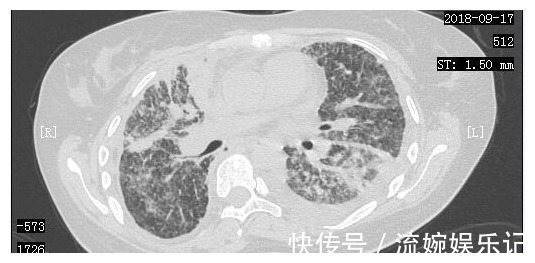

在经历了短暂的绝望后,小周一家决定齐心协力,积极进行抗癌治疗。2018年9月7日,小周进行了胸腔穿刺抽液,同时进行了胸腔灌注化疗。2018年9月14日,小周来到了我们医院进行治疗,复查了胸部CT,当时的胸部CT显示肺部一般情况非常差。

我院肿瘤科医生根据小周的一般情况,也马上下了病危,提醒小周家属,随时可能出现去世的可能。在小周父母很伤心的时候,反而是小周心态积极,安慰父母:我们就积极治疗吧,能够到哪一天就到哪一天吧。同时,根据小周的病情状况,肿瘤科医生也马上制定了治疗方案,给予了小周化疗以及靶向治疗,通过调整靶向药物,小周从2018年9月23日开始口服某靶向药物治疗。经过治疗,小周的一般情况居然逐渐好转起来,同时也顺利出院回家进行调养,到2019年4月12日,小周又再次在我院复查了CT,我们惊喜地发现,她双肺的病灶明显减少,甚至几乎看不到了。